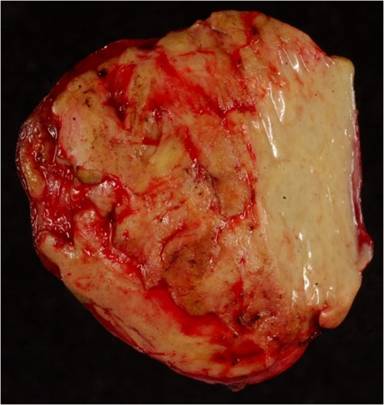

The pathological study showed a xantohogranuloma type histiocytary proliferation and the presence of cells with relevant pleomorphism, frequent binucleations and evident nucleolus, with homogeneous background of marked mixed inflammation with the predominance of polymorphonuclear neutrophils (Figure 3). The histiocytary origin was confirmed by immunohistochemical staining with the CD68 antibody (Figure 4ab). The cell proliferation rate, defined by the expression of the Ki67 antibody, was 10%. Differential diagnosis was made between malignant fibrohistiocytoma and inflammatory pseudotumor. The severity of the inflammatory component and the low proliferation rate of histiocytary cells were highly suggestive of a pseudotumoral lesion. On the basis of these findings, final pathological diagnosis was of inflammatory pseudotumor.

Figures 3. Hematoxylin-eosin staining samples showing proliferation of xanthogranuloma type histiocytary cells (HC) and the presence of some pleomorphic cells (PC), with a homogeneous background of marked mixed inflammation with the predominance of polymorphonuclear neutrophils (N). The pleomorphic cells presented binucleation with evident nucleolus. |